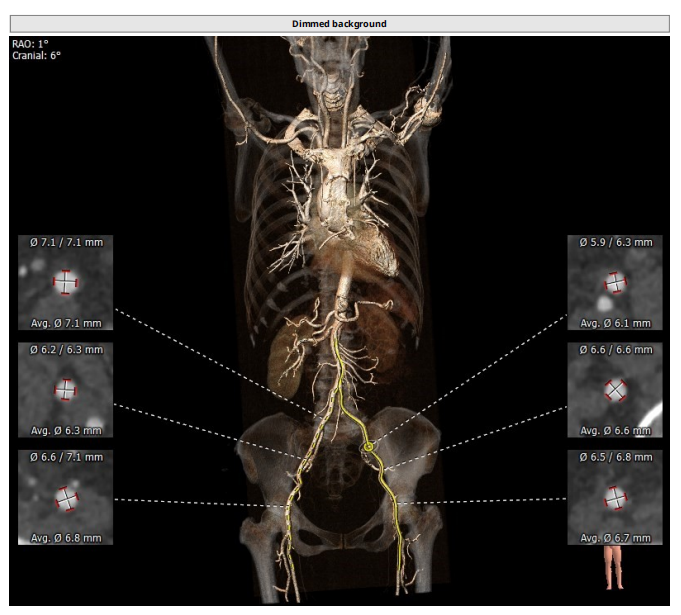

术前CT评估

整体情况

瓣环:16.9mm,左室流出道:16.7mm

STJ:23.9mm,升主动脉:31.4mm

瓣叶增厚 右冠高度:10.9mm,左冠高度:9.5mm

心室大小可

工作体位:LAO:12°CRA:5°,左冠切线位:LAO:26° CRA:19°

右股为主入路